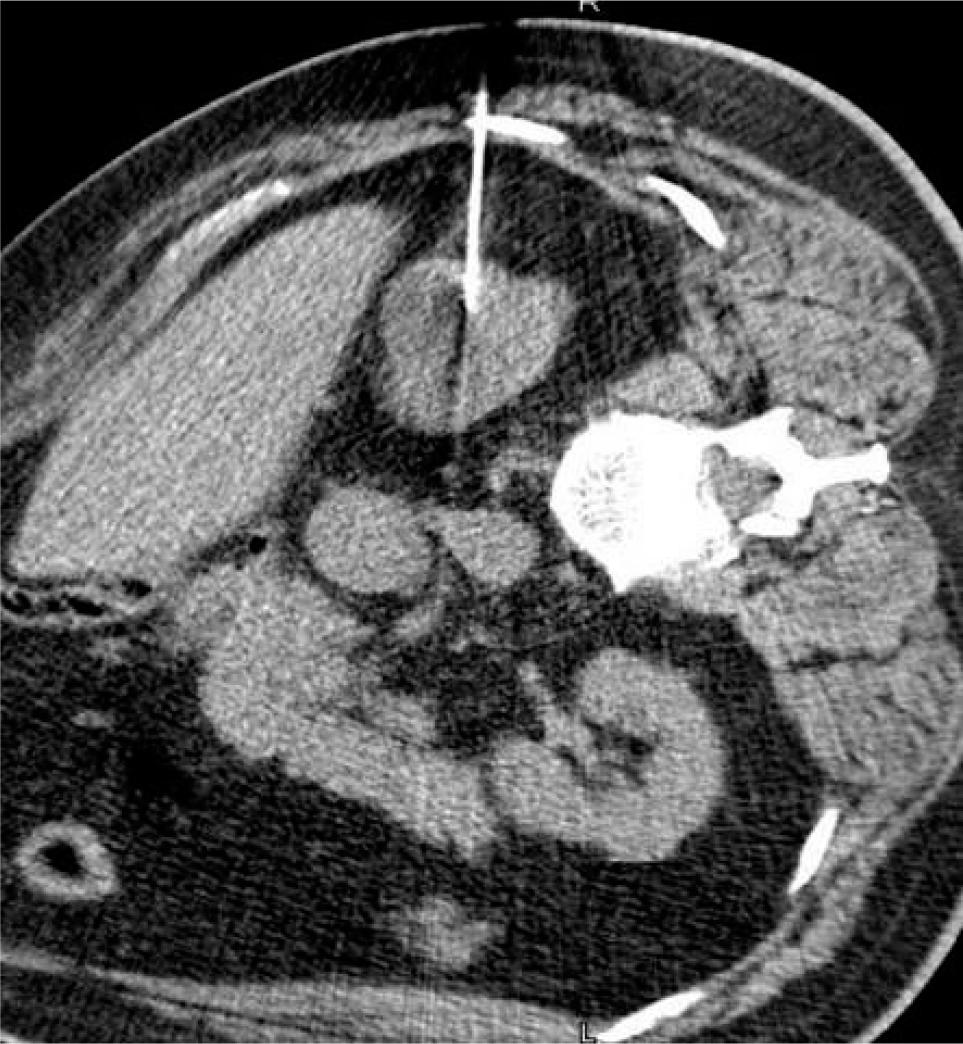

Guideline recommendations

Strong retrospective results in the setting of a lack of available randomized trial data have resulted in relatively broad guideline recommendations for the use of RFA. The AUA notes that thermal ablation, “should be considered as an alternative approach for the management of cT1a renal masses < 3 cm”(12, 13). The EAU states that thermal ablation can be offered, “to frail and/or comorbid patients with SRMs.” They caution that, “low quality studies suggest high disease recurrence rates after RFA of tumors > 3 cm (14) (Figures 4A and 4B).

Figure 4: (A) Microwave antenna seen in 3 cm, upper pole renal mass. (B) Follow-up at 3 months shows residual enhancement of the superior aspect of the lesion consistent with residual tumor, demonstrating the importance of follow-up.